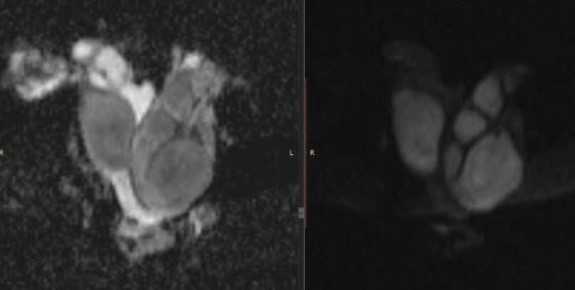

МРТ малого таза в сагиттальной плоскости. В структуре яичника отмечается неправильной формы эндометриоидная (“шоколадная”) киста, заполненная вязким геморрагическим содержимым.